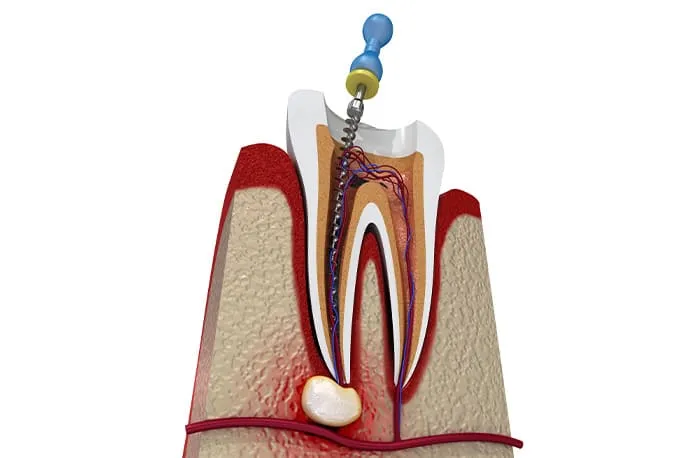

虫歯が重度に進行すると、虫歯菌が歯の神経まで感染し、歯の内部にある神経を取り除く必要が出てくることがあります。

根管治療とは、文字通り「歯の神経が入っている根の管(根管)」に対して行う治療です。 もし根管治療を行わずに放置してしまうと、細菌が歯の根の先にたまり、やがて根の先が化膿してしまいます。その結果、強い痛みが出たり、歯ぐきや頬が腫れたりすることもあります。

①根管拡大

ニッケルチタンロータリーファイルを使用し、根管を適切な形に広げながら、内部に存在する細菌を物理的に取り除いていきます。

根管の長さの測定

根管口が見つかったら、ファイルと呼ばれる細い針金のような器具を根の先まで挿入し、根管の正確な長さを測定します。この工程が、治療の精度を左右する重要なポイントになります。

根管の清掃・消毒

測定した長さに合わせて、柔軟性のあるニッケルチタンファイルで根管を最小限に広げます。同時に消毒剤を使用し、根管内部を徹底的に洗浄・消毒していきます。